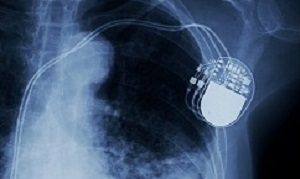

Patients around the world are suffering pain and many have died as a result of faulty medical devices that have been allowed on to the market by a system dogged by poor regulation, lax rules on testing and a lack of transparency, The Guardian reports an investigation has found. Pacemakers, artificial hips, contraceptives and breast implants are among the devices that have caused injuries and resulted in patients having to undergo follow-up operations or in some cases losing their lives. In some cases, the implants had not been tested in patients before being allowed on to the market.

Pacemakers, artificial hips, contraceptives and breast implants are among the devices that have caused injuries and resulted in patients having to undergo follow-up operations or in some cases losing their lives. In some cases, the implants had not been tested in patients before being allowed on to the market.

The report says in the UK alone, regulators received 62,000 “adverse incident” reports linked to medical devices between 2015 and 2018. A third of the incidents had serious repercussions for the patient, and 1,004 resulted in death. In the US, the Food and Drug Administration (FDA) has collected 5.4m “adverse event” reports over the past decade, some from manufacturers reporting problems in other parts of the world. These included 1.7m reports of injuries and almost 83,000 deaths. Nearly 500,000 mentioned an explant – surgery to remove a device.

Examples of failure in the market include: replacement hips and vaginal mesh products sold to hospitals without any clinical trials; patients relying on faulty pacemakers when manufacturers were aware of problems; complications with hernia mesh that ruled one of Britain’s top athletes out of competing for years; regulators approving spinal disc replacements that later disintegrated and migrated in patients; surgeons admitting they were unable to tell patients about the risks posed by implants because of a lack of central registers; and patients in Australia being given devices that the regulator has approved on the basis they have been approved in Europe.